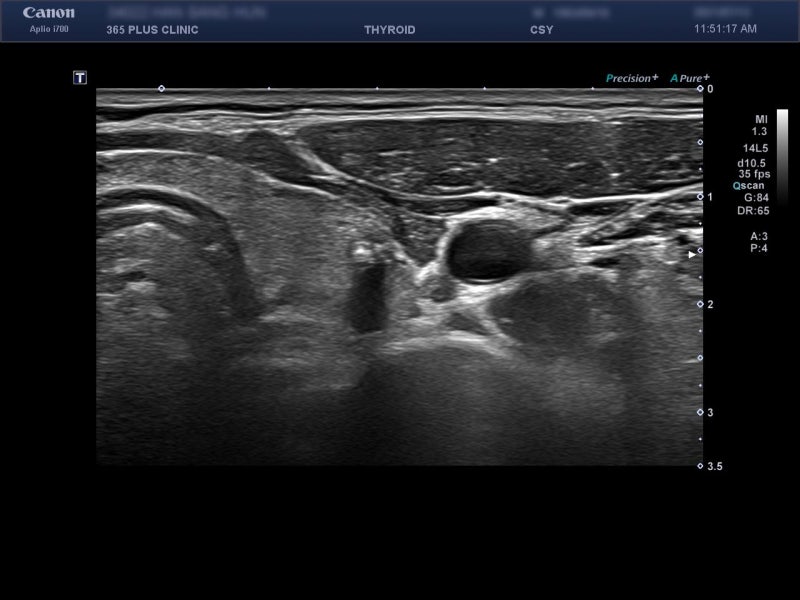

특별한 과거력, 가족력이 없는 40대 후반의 여성이었습니다.지난 1년 동안 식사량, 운동량의 변화 없이 똑같이 생활하고 있었는데 체중 감소가 2kg 있었다고 했습니다.체중 감소에 대한 평가 중 하나로 갑상선 초음파 검사를 실시했습니다.

앞 이미지 다음 이미지 상선초파 – 최선 [검색] 1. 갑상선 혈관성 증가없이 정상적인 에코성. 2. Rt 갑상선-마이크로/거시석회화를 동반한 7mm 저친환경 병변, mid, K-TIRADS53. Lt 갑상선 – 1.3cm 혼합 에코 병변, mid, K-TIRADS 3.4. 양쪽 갑상선에 몇 개의 작은 낭종이 있습니다.[결론] K-TIRADS 5 [권장] 단기 팔로우업 또는 FNARADS 5 [ ].환자분과 상의 후 본원에서 FNA를 시행하였습니다。

하남갑상선 – papillary thyroid carcinoma조직검사 결과 위와 같이 papillary thyroid carcinoma(갑상선 유두암)로 진단되었습니다.수술을 위해 상급병원을 의뢰했어요. 잘 치료되었으면 좋겠어요.하남갑상선갑상선암 개요 가정의학 제4판 / 대한가정의학회 편저 / 의학출판사갑상선암은 내분비계 암 중 가장 흔한 암입니다.갑상선암은 여포세포 기원의 암인 유두암, 여포암 및 미분화암 그리고 C세포 기원의 수질암으로 나눌 수 있습니다.그 중 유두암과 여포암을 분화암이라고 합니다.국내에서는 2011년 유두암이 97%, 여포암이 1.4%이며 이는 해리슨내과학에서 제시하는 발생률에 비해 유두암의 비율이 약간 높습니다. 갑상선암 위험요인 가정의학 제4판 / 대한가정의학회 편저 / 의학출판사- 방사선조사-TSH수용체반응도-성장호르몬과잉분비-갑상선암유발유전자(RET,TRK,ras,BRAF,p53 등)갑상선암의 임상증상 가정의학 제4판/대한가정의학회 편저/의학출판사갑상선암은 거의 자각 증상이 없습니다.상대적으로 흔한 증상은 자신이나 다른 사람에 의해 또는 진찰에서 우연히 발견되는 통증이 없는 목 덩어리이며, 이 덩어리 또는 커진 갑상선을 검사하면서 갑상선암을 발견합니다.다음과 같은 징후가 있으면 갑상선암을 배제하기 위해 갑상선에서 진료를 받고 목 주변부 림프절 진찰을 포함한 평가를 실시해야 합니다. 그 후 필요에 따라 갑상선 초음파도 실시합니다.[갑상선암 검진이 필요한 징후] – 갑상선 비대- 이유없이 계속되는 쉰목소리-소아 갑상선 결절-갑상선종-경부림프절 비대가 동반되는 갑상선 결절-통증없이 갑자기 커진 갑상선 결절갑상선암 진단검사 가정의학 제4판/대한가정의학회 편저/의학출판사1) 검사실검사 – 갑상선기능검사, 혈청 칼시토닌검사 등 2) 갑상선 초음파검사[초음파검사상 악성을 시사하는 소견] – 앞뒤가 긴 모양(tallerthan wide) – 침상(spiculated) 혹은 불규칙한 경계-고형성분의 현저한 저친환경-미세 및 거대석회화-경부림프절 비대 동반3) 가는 바늘흡인세포검사(FNAC) 갑상선 초음파 상결절이 악성일 가능성이 있으면 FNAC를 실시합니다.365플러스내과의원 경기도 하남시 미사강변동로84번길 39 에코타워 2~5층하남시 망월동 미사역 인근 365플러스내과 검진센터에서는 실력 있고 경험이 풍부한 영상의학과 원장에게 매우 좋은 사양의 초음파 기기를 사용하여 갑상선 초음파 검사를 받을 수 있습니다. 특히 채원장은 예전에 서울성모병원(고속터미널역 근처 가톨릭대학교 서울성모병원)에서 근무할 때 갑상선 파트에 있으면서 주로 갑상선 초음파와 갑상선 세침 검사를 하셨다고 합니다. 🙂 갑상선암 의심 병변 발견 시 본원에서 FNA도 가능합니다.하남갑상선검사는 365플러스내과를 권장합니다.감사합니다。하남갑상선초음파하남갑상선초음파하남갑상선하남갑상선하남갑상선하남갑상선하남갑상선하남갑상선